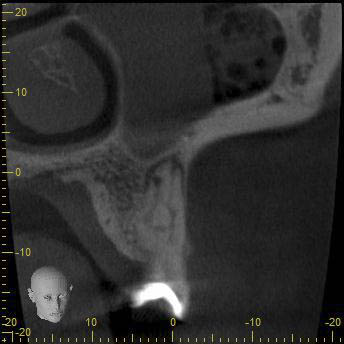

BN2627_DVT (17 von 17) Veröffentlicht 1. Dezember 2014 am 344 × 344 in Unerwartete Anatomie Zahn 26, 27- die WF